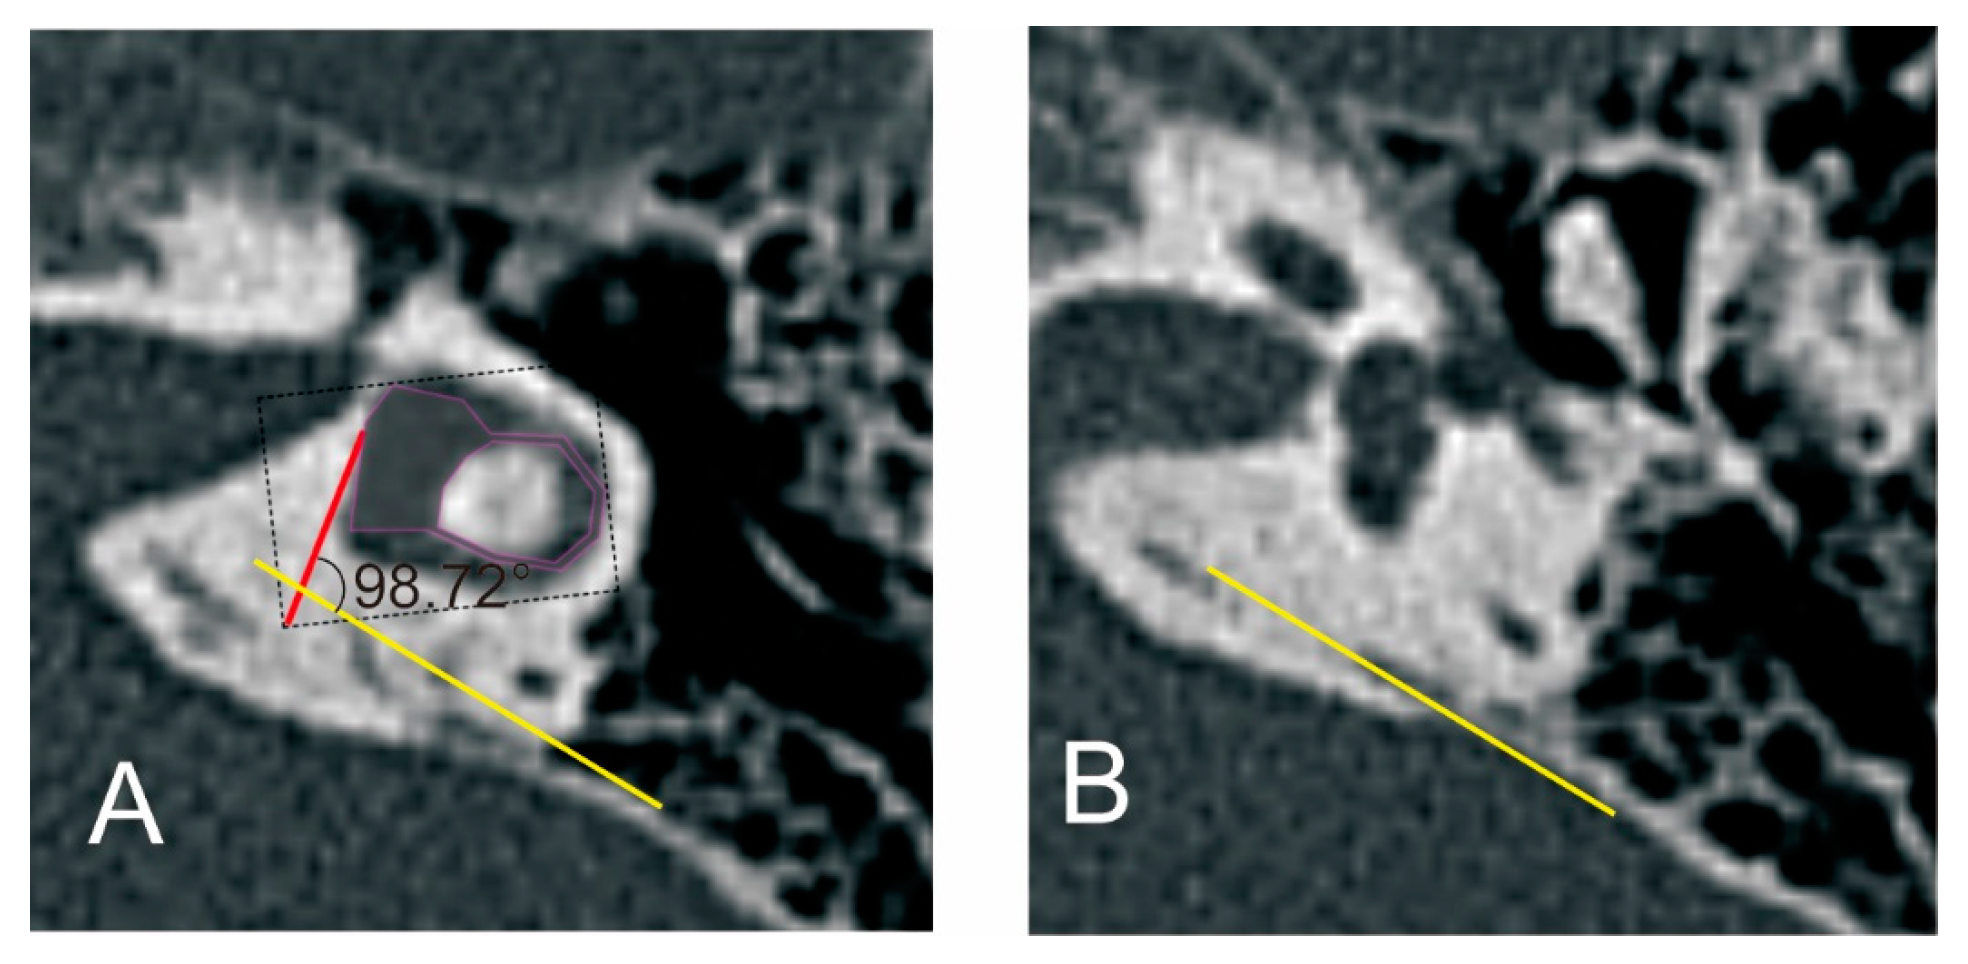

ATVA was measured as described by Bächinger et al. (http://links.lww.com/MAO/A755, accessed on 14 September 2022) [15] using a specifically developed software (downloaded at https://github.com/DanielZuerrer/CoolAngleCalcJS) (Figure 6). The first image imported to the software showed the horizontal semicircular canal (SCC) and the vestibule. The magenta-shaded area form was adjusted to fit into the boundaries of the vestibule and the horizontal SCC (especially the boundaries of the vestibule), and the first red line was defined. The second imported image showed the distal portion of the VA. A yellow line was adjusted to be parallel with the distal portion of the VA. ATVA was determined between the first red line and the second yellow line. And ears were further divided into ears with ATVA ≤ 120°,120° < ATVA < 140°, and ATVA ≥ 140°.

Figure 6.

The measurement of the angular trajectory of the vestibular aqueduct (ATVA). (A) Images show the horizontal semicircular canal (SCC) and the vestibule. (B) Images show the distal portion of the vestibular aqueduct (VA). ATVA refers to the angle between the red line and the yellow line.